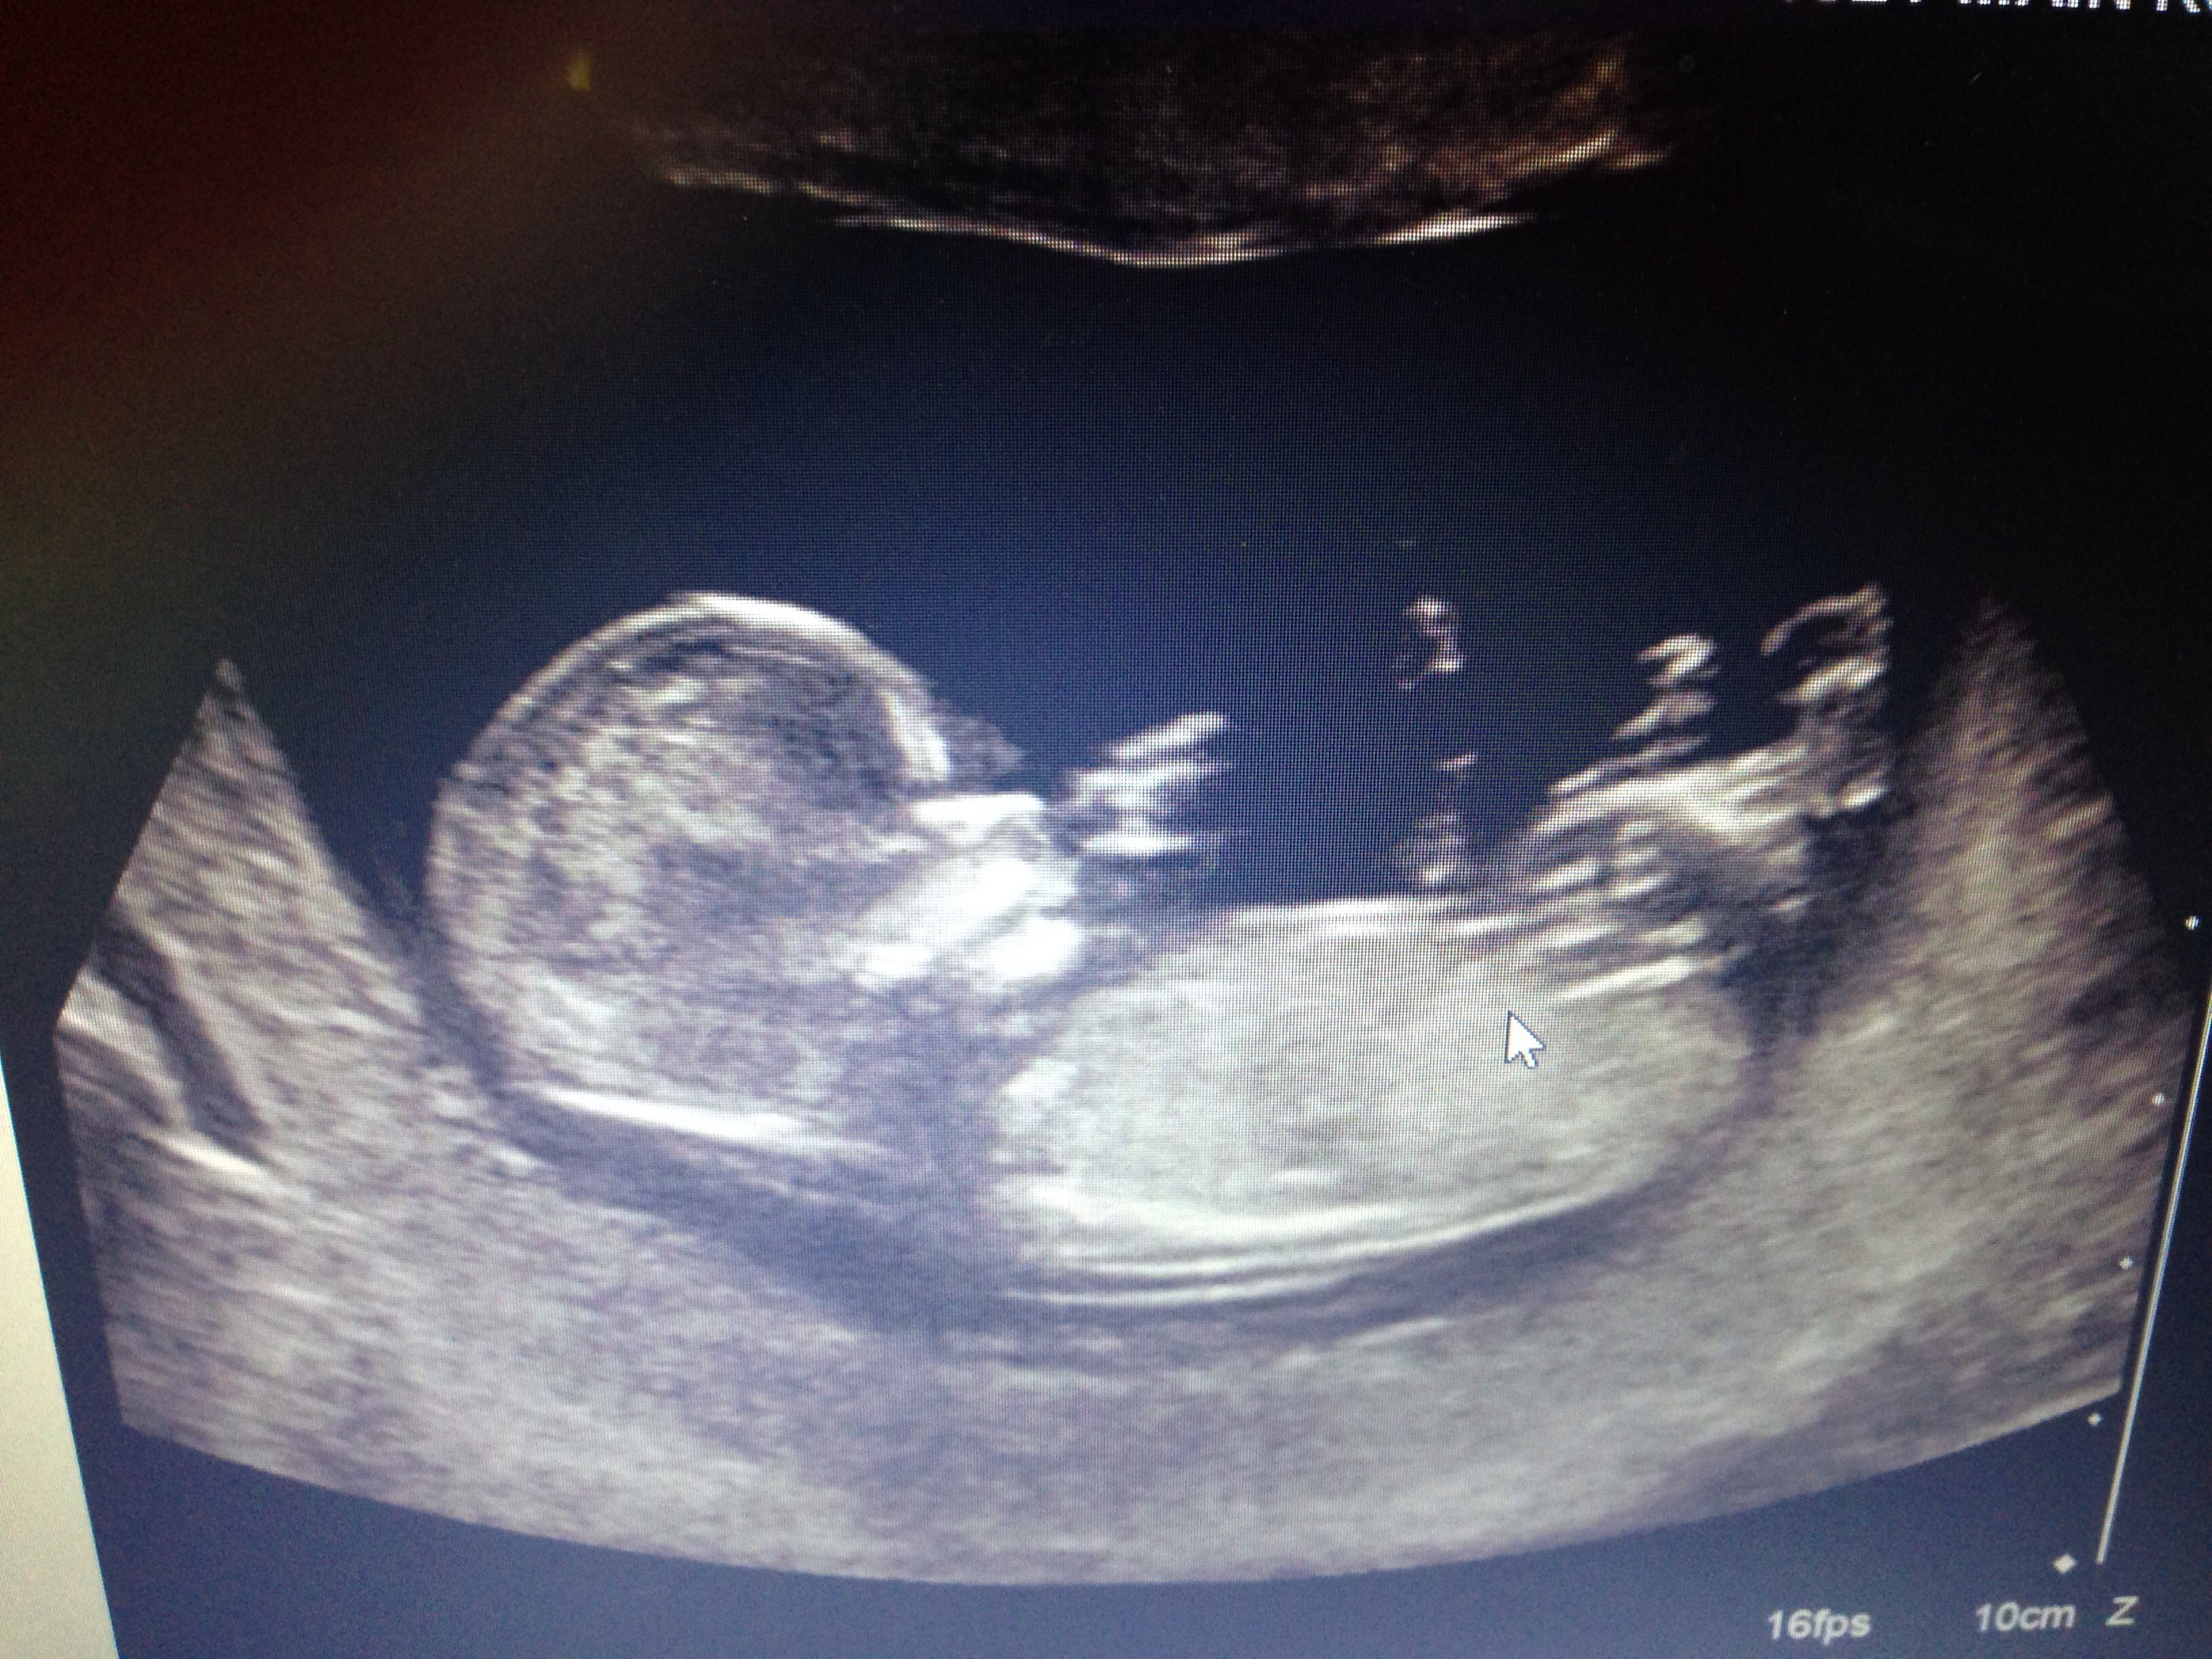

My NT scan was yesterday. NT measurement was good - 1.5ish. Fibroids have been stable so far. I had blood drawn for the MaterniT21 test since I'm an old lady. Baby 3.0 was rolling around and swinging at an invisible enemy.